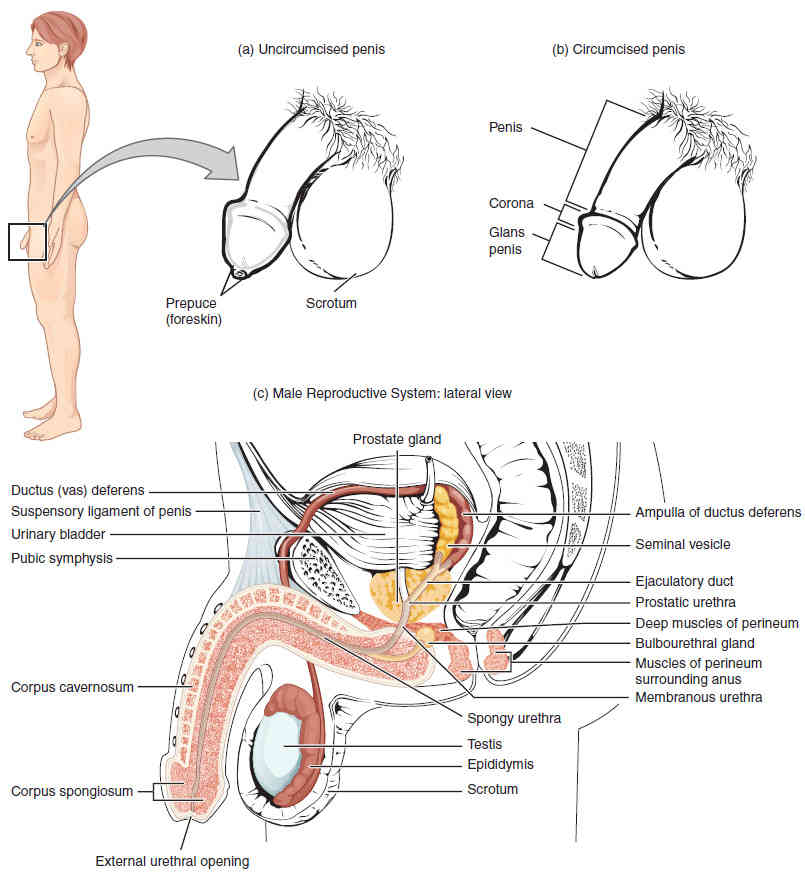

This page is under construction. For now, it is just a resource of the images found in the OpenStax Anatomy and Physiology Handbook. It wil slowly change into a revision tool. Each slide has a number. Use this to refer to the slide. When completed, it will have an unlabelled section, with labelled slides in parallel. On the unlabelled slides, write your answer and use the labelled slide to assess yourself. Keep track by also noting the number on each slide. Improvement at each attempt is important, more so than full marks on a first attempt.